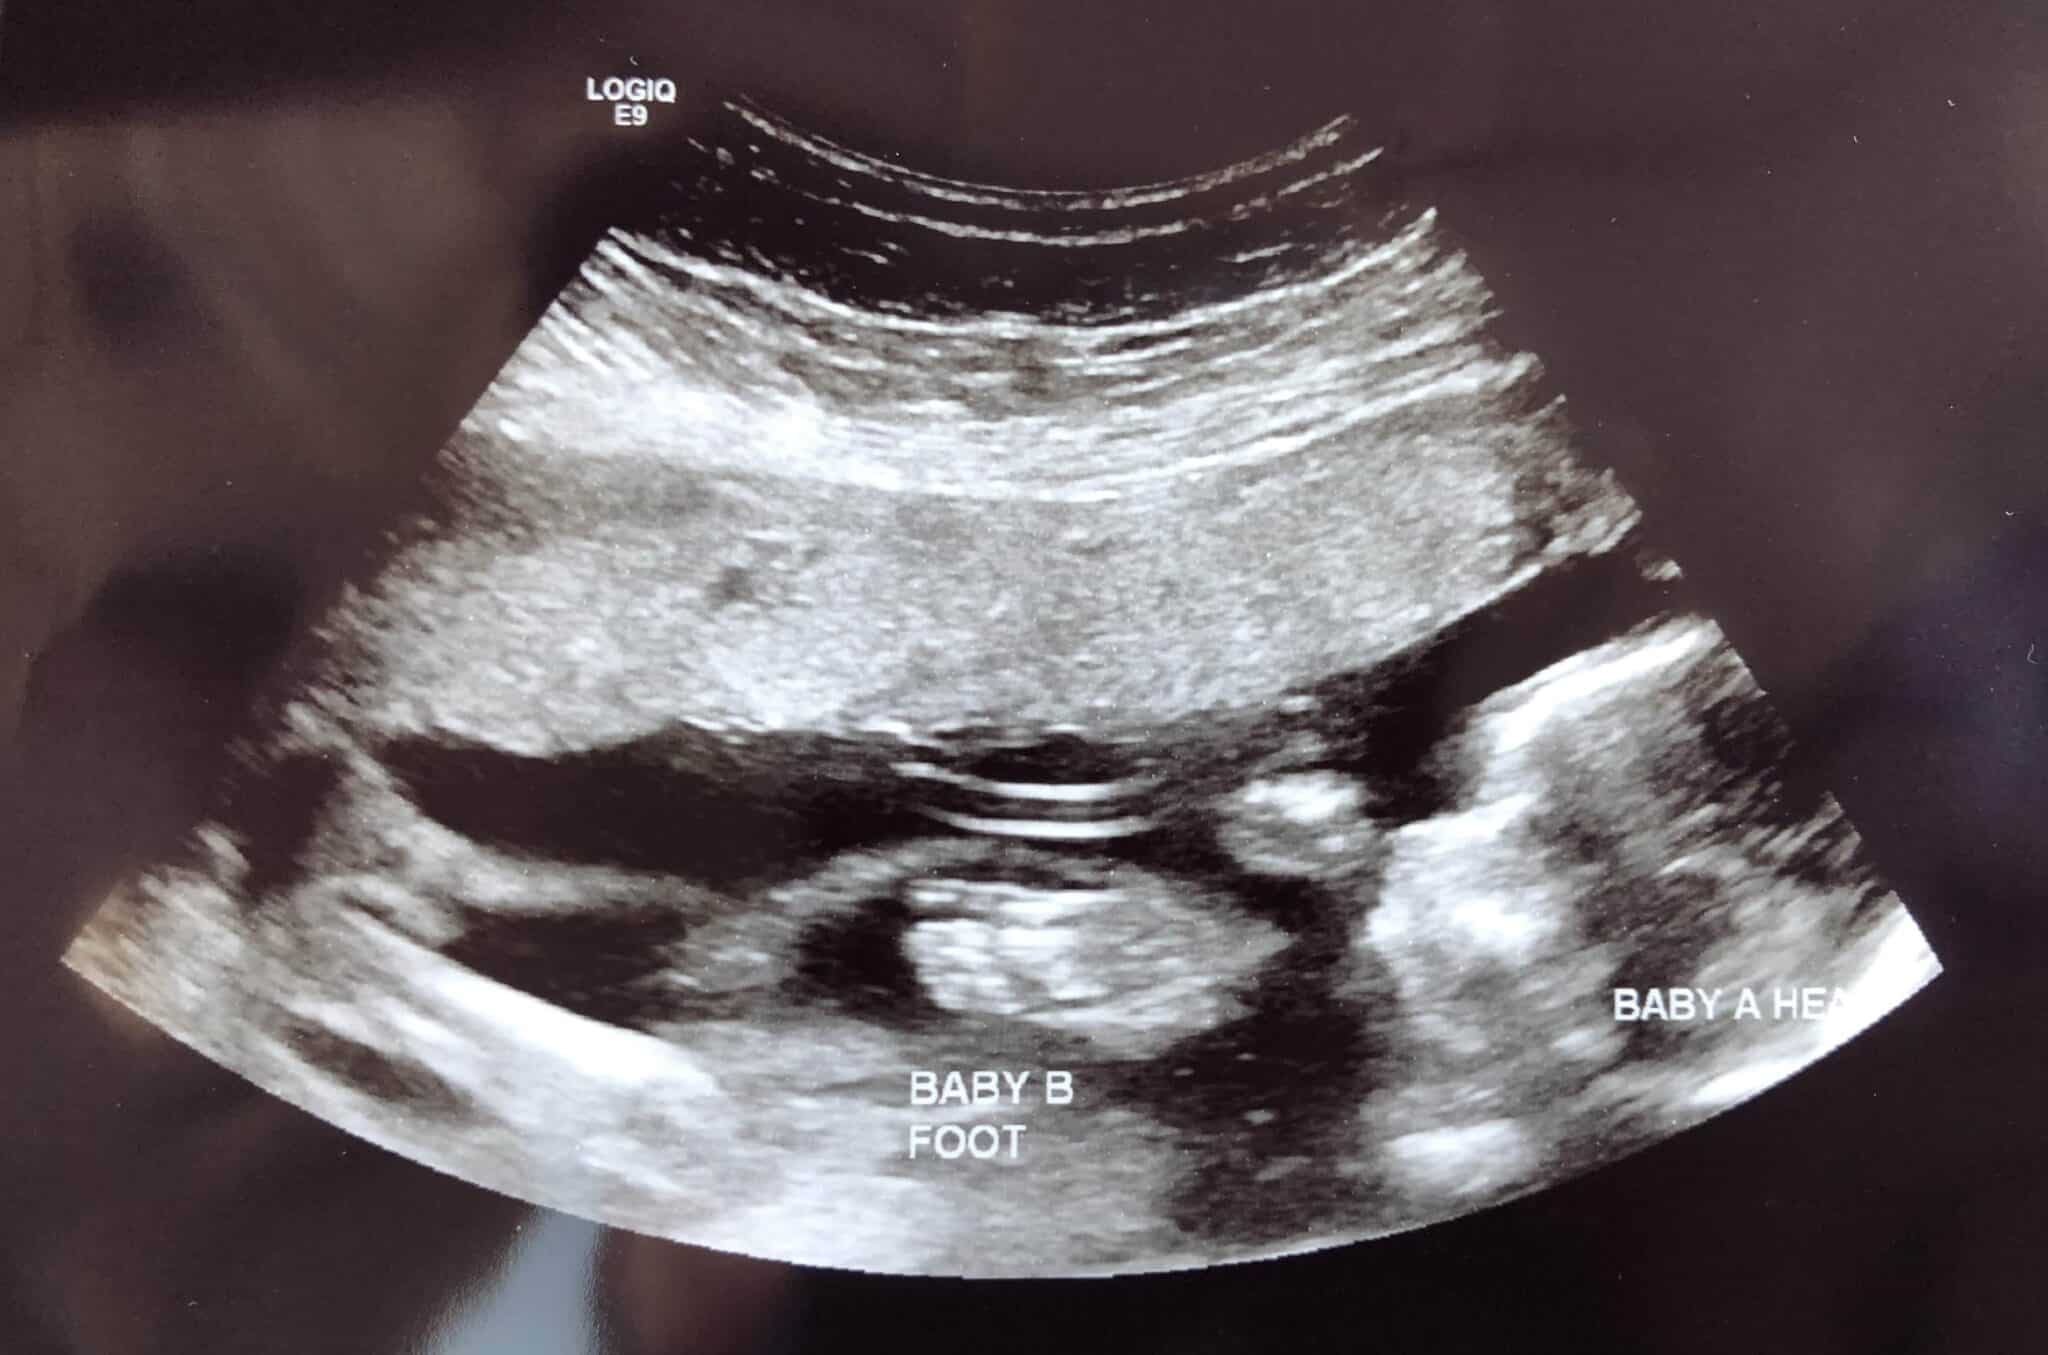

Ultrasound Photos at 19 Weeks Pregnant With Twins